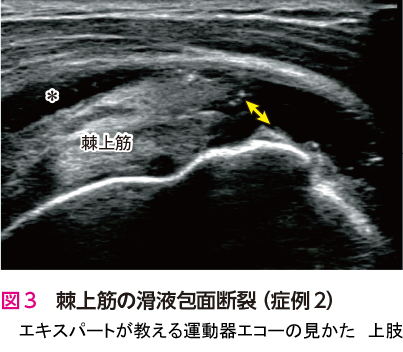

この方は肩関節痛を主訴に来院されました.上方の腱板(棘上筋)を長軸像で確認すると,腱板の表層に陥凹が認められ(図1🅑

)上腕骨表面にも不整像が認められています(図1🅑

).腱板の変性断裂に伴う変化です.断裂部に水腫がある症例では診断が容易です.